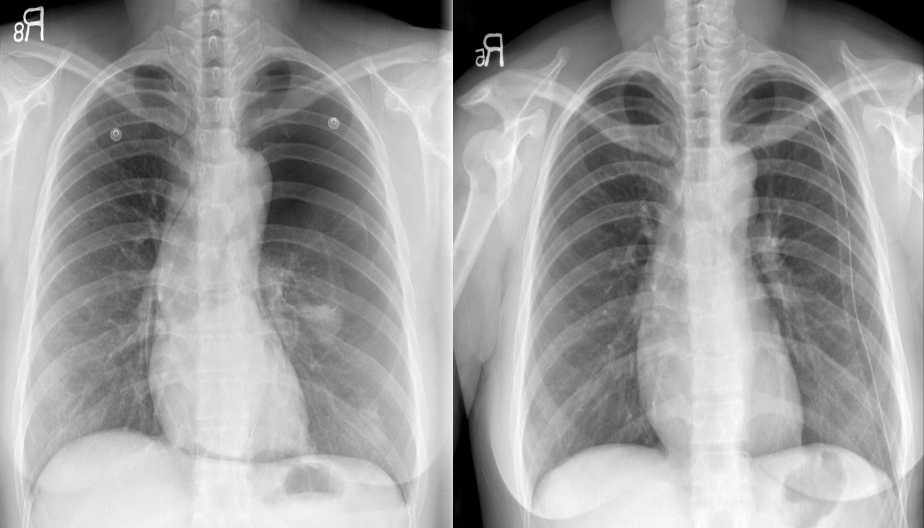

Congestive cardiac failure. There are large bilateral pleural effusions. The heart is enlarged although it is difficult to measure it precisely because the pleural fluid obscures its borders. //– Chest x-ray pleural effusion both, in right costrophrenic & left meniscus sign -

Pericardial effusion. The heart is greatly enlarged. The outline is well defined and the shape globular (Flask - bottle). The lungs are normal. The cause in this case was a viral pericarditis. // Flask shaped, pericardial effusion